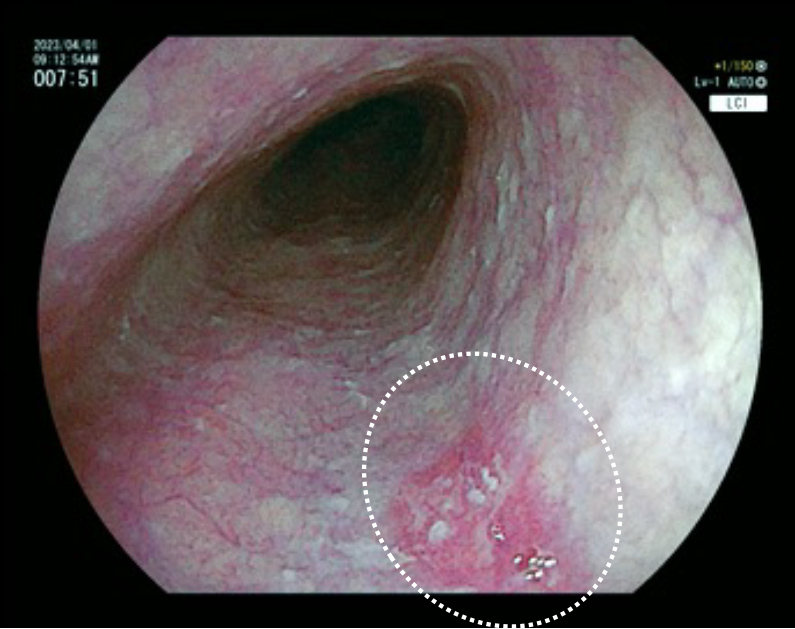

内視鏡検査の所見例

食道と胃の境 食道炎

内視鏡検査の所見例

食道と胃の境 食道炎

特殊光で炎症を強調して観察